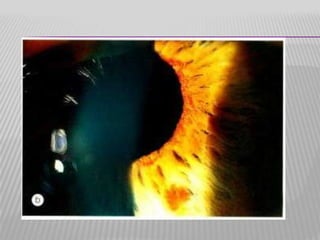

NEW VESSELS

Irregular size

Irregular course

Branching

Located on surface

NORMAL IRIS VESSELS     Uniformsize Radial course No branching Located in stroma NEW VESSELS     Irregular size Irregular course Branching Located on surface